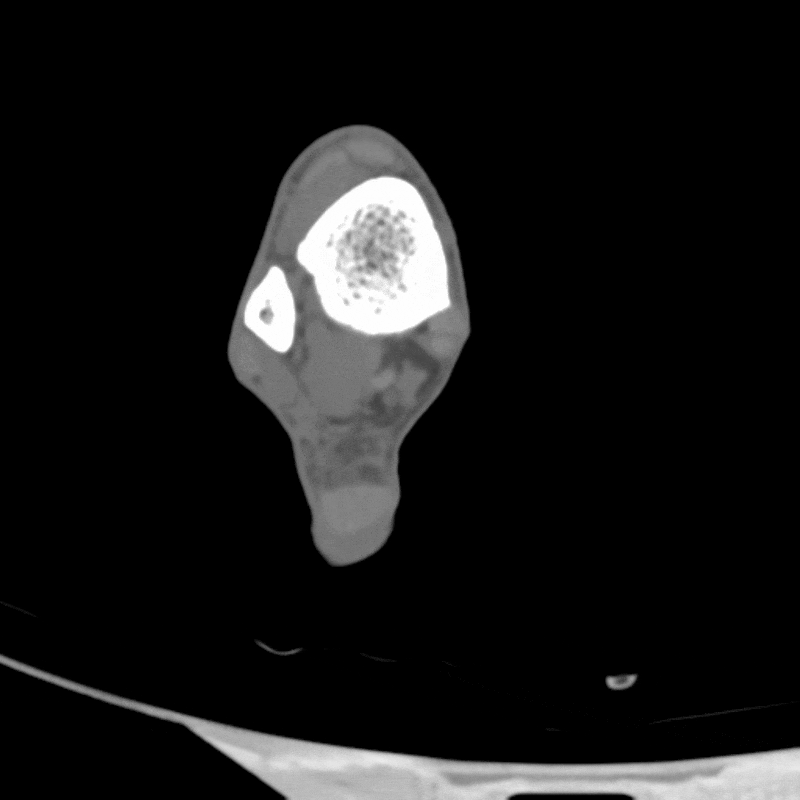

Gout is a type of inflammatory arthritis caused by a buildup of uric acid crystals in the joints and surrounding tissues. These deposits trigger painful flares and long-term joint damage if left untreated. One of the key challenges in diagnosing gout is distinguishing uric acid crystals from other materials—particularly calcium deposits, which can appear similar on standard CT scans. This distinction is critical, as treatments for gout differ significantly from those used for calcium-based conditions like pseudogout or calcific tendinitis. Without a clear diagnosis, patients may receive the wrong treatment or face delays in care.

Dual energy CT addresses this problem by capturing images at two different X-ray energy levels. Because uric acid and calcium absorb X-rays differently depending on the energy, DECT can separate the two and highlight urate deposits directly on the images. This gives clinicians a non-invasive way to confirm gout, especially in difficult cases where fluid aspiration isn’t possible. DECT can also measure the total volume of crystal burden, allowing physicians to track how well urate-lowering therapies work over time. By improving both diagnosis and disease monitoring, DECT supports more accurate, tailored treatment for patients with gout.

Figure A: Dual energy CT images of the foot, to be used for identifying gout.

Figure B: The images of the foot from Figure A after post-processing filters have been applied, highlighting the presence of urate crystals in purple and calcified structures in green.

Figure C: Volume rendering of the imaging from Figure B, demonstrating the extent of urate crystal and calcified structures in 3D.